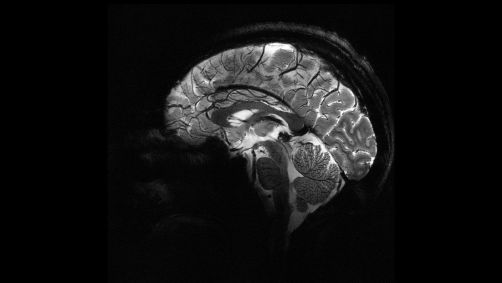

Por que o envelhecimento do cérebro varia de pessoa para pessoa?

Pesquisadores estão descobrindo insights mais profundos sobre como o cérebro humano envelhece e quais fatores podem estar ligados a um envelhecimento cognitivo mais saudável, incluindo exercícios físicos, evitar o tabaco, falar uma segunda língua ou até mesmo tocar um instrumento musical.

Alguns aspectos das habilidades cognitivas na idade avançada podem estar relacionados aos resultados dos testes por volta dos 11 anos de idade, de acordo com um artigo de revisão publicado nesta quinta-feira (7) na revista Genomic Psychiatry da Genomic Press New York.

O artigo, baseado em dados dos estudos do Lothian Birth Cohorts na Escócia, sugere que cerca de metade das variabilidades na cognição das pessoas em idades mais avançadas — por que algumas pessoas podem ter declínio cognitivo maior do que outras? — podem já estar presentes em suas infâncias.